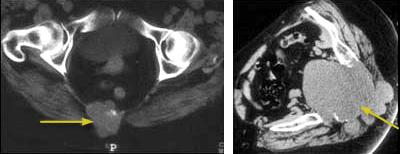

CT scans showing chordomas

Cross-sectional CT scans of the pelvis (left) and the base of the spine (right) show a chordoma in the sacrum.